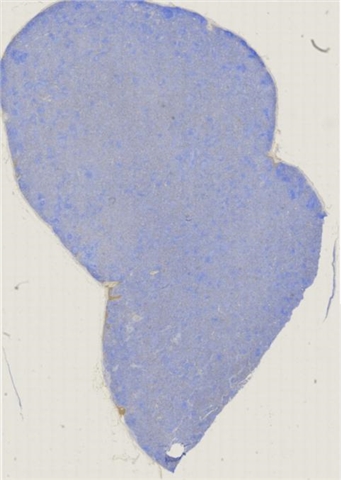

案例3 (6862)

性别:       年龄:65

患者详情: 患者3月余前在当地社区卫生服务中心体检发现血肌酐升高(109.8umo/L),无明显尿量减少,无颜面下肢浮肿无腰酸腰痛,无肉眼血尿,无关节疼痛,无皮疹红斑,开始未重枧及进一步诊治。10余天前患者到中山医院复查生化提示“肌酐200umol/L、尿素7.3mmol/L、尿酸637umol/L、白蛋白34g/L、球蛋白66g/L、蛋白电泳β15.0%、蛋白电泳Y42.6%”,同时其它检查提示“血lgG4 54.20g/L”。 CT:纵隔及双侧腋下多发肿大淋巴结,肺动脉干稍増粗,主动脉硬化,扫及双肾饱满,后腹膜发淋巴结。 PET-T:全身多区域淋巴结肿大、双侧泪腺、双侧颌下腺及胰腺体尾部饱满、双肾实质肿胀,左侧头皮局部增厚,伴FDG代谢增高,鼻咽顶后壁及前列腺腺体FDG代谢增高,上述病灶首先考虑IgG4相关性疾病所致可能,建议暖股沟淋巴结活检病理明确除外淋巴瘤。

大体所见: 结节一枚3*3*2cmA-C。

医院: 上海交通大学医学院附属仁济医院